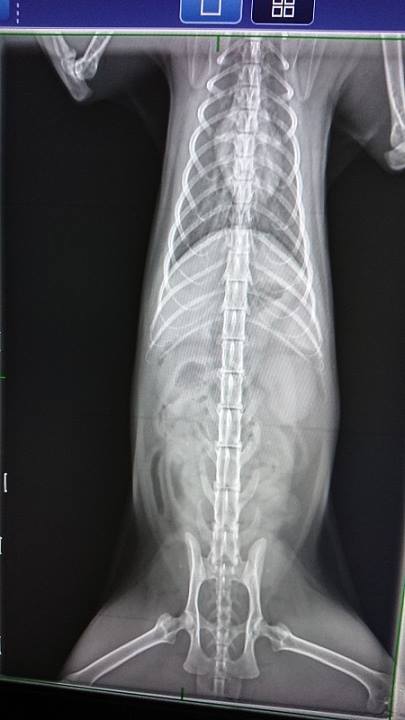

且此次回所全身、頭部搖晃不停,

先行就醫,檢測應為農藥中毒,

影響神經所致。

動物近況說明: 經過治療後,搖晃與發抖的狀況已經緩和許多,情緒也逐漸穩定,但依舊會顫抖不止,仍然要繼續治療與觀察。